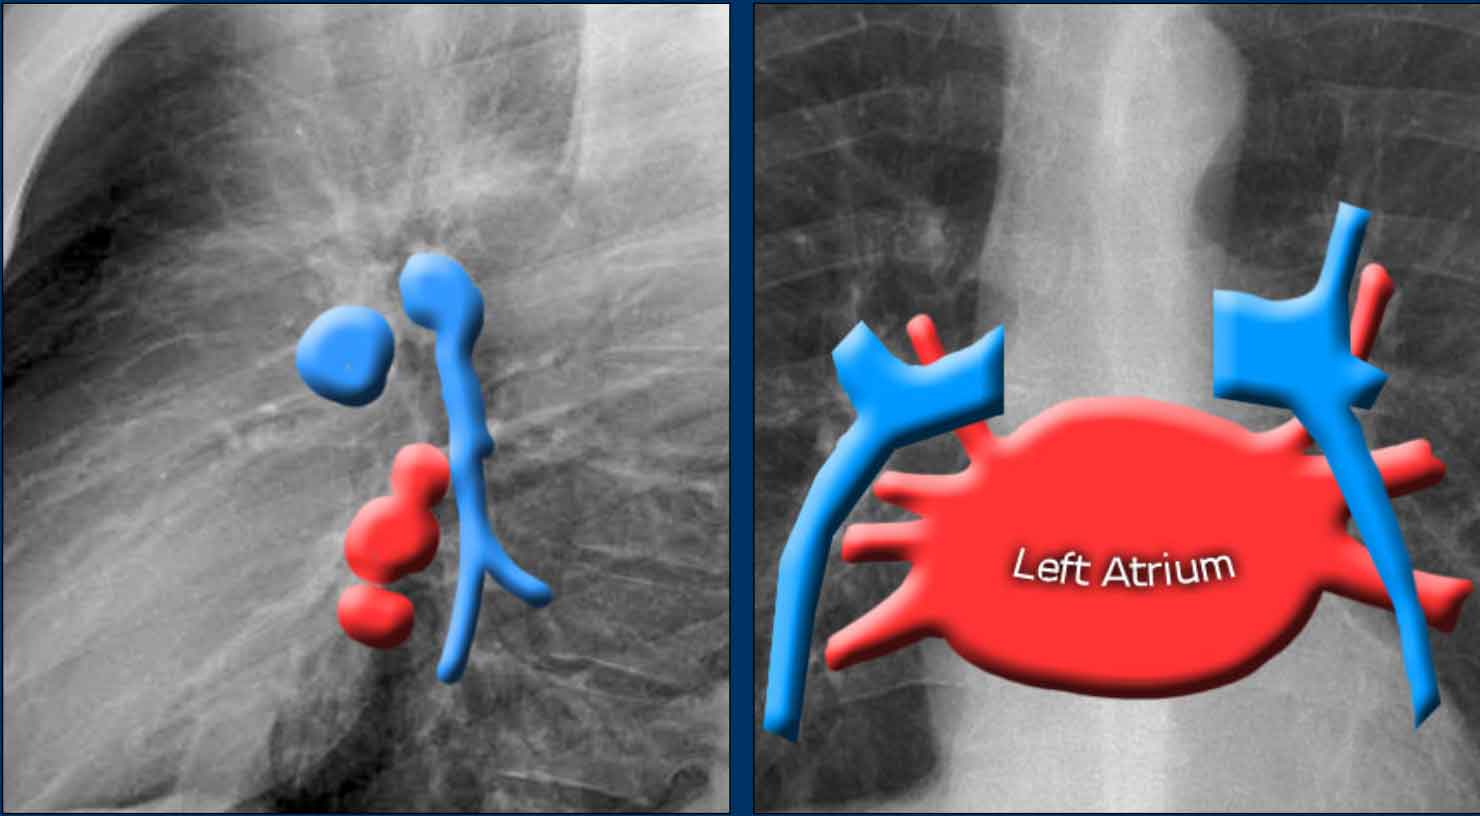

An important anatomical consideration is that the left hilum is normally situated higher than the right.

This relationship arises from the course of the pulmonary arteries: the left pulmonary artery arches over the left main bronchus, while the right pulmonary artery courses anterior to the right main bronchus, which is typically positioned lower than its left counterpart.

In a minority of cases, the hila may be at the same level, but the right hilum should never be higher than the left.

In this illustration, lower lobe pulmonary arteries are colored blue to indicate deoxygenated blood.

These arteries have a more vertical orientation compared to the pulmonary veins, which run more horizontally toward the left atrium, located inferior to the level of the main pulmonary arteries.

On lateral chest radiographs, both pulmonary arteries and veins are identifiable and should not be misinterpreted as lymphadenopathy. Occasionally, pulmonary veins may appear prominent.

The left main pulmonary artery passes superior to the left main bronchus and lies higher than the right pulmonary artery, which courses anterior to the right main bronchus.

The included images are thick-slab sagittal CT reconstructions of the thorax, which enhance visualization of hilar structures.

The lower lobe pulmonary arteries descend from the hilum in a vertically oriented fashion.

Radiographically, these vessels are colloquially referred to as the “little finger” due to their size and shape, approximating that of a little finger (1).

On PA chest radiographs, the "little finger" of the right lower lobe pulmonary artery is visible in approximately 94% of normal individuals, while on the left side it is visible in about 62% (1).